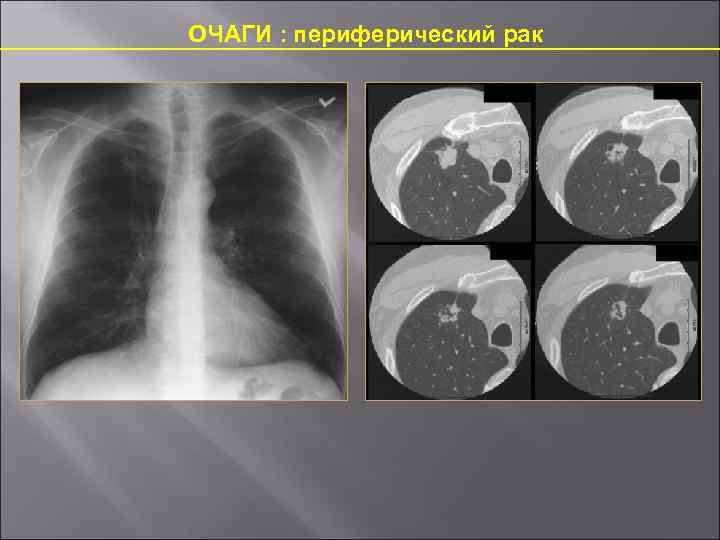

Визуализация и диагностика неинвазивного аспергиллеза с помощью КТ